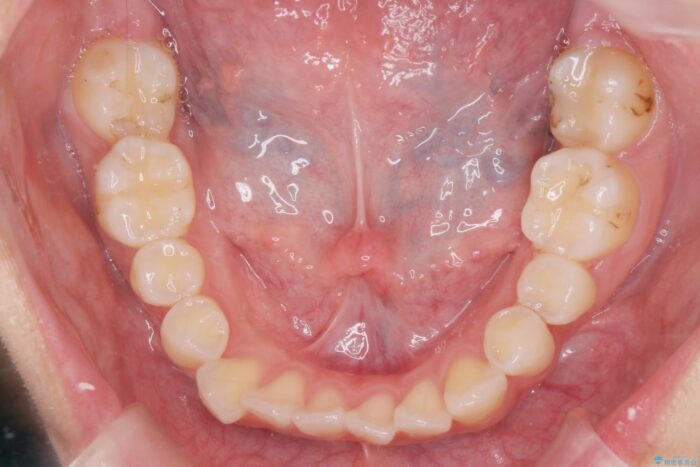

噛まない前歯と捻じれてしまった歯を改善したいと、矯正治療を希望された患者様です。

マルチブラケットを用いた非抜歯のワイヤー矯正で噛み合わせと歯並びを改善していきます。